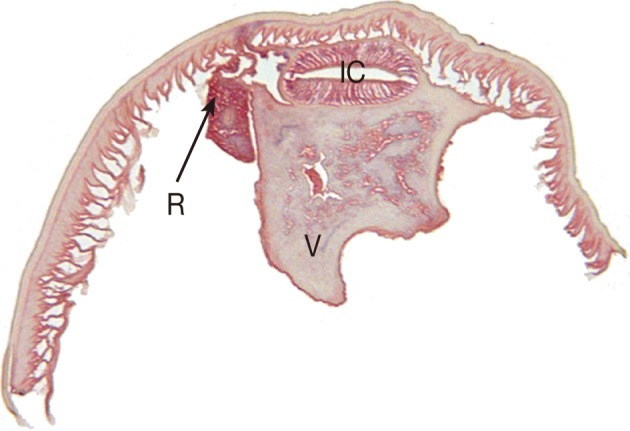

The intestinal cecum, confirmed by section of the anterior part of the worm, was 1.1 mm in length, stretching to the middle level of the ventriculus. The tail, 0.20 mm in length, was conical with a terminal mucron. The presence of an intestinal cecum without ventricular appendage was easily observed in the transverse section of the worm (

Fig. 2). All of these findings readily identified the specimen as a third stage larva of

Pseudoterranova decipiens. After removal of the larva, the patient returned home and followed up uneventfully.

Fig. 2Transverse section of the P. decipiens larva. Note that the intestinal cecum (IC), ventriculus (V), and renette cell (R) are seen.